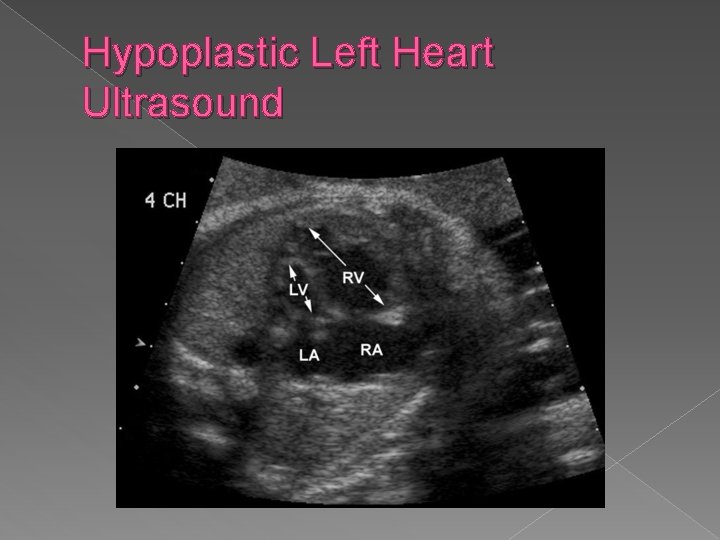

Hypoplastic Left Heart Syndrome � A small left ventricle results from decreased blood flow into or out of the left ventricle. The primary abnormalities include aortic atresia, aortic stenosis (coartation of the aorta is present in 80% of cases), and mitral valve atresia. Sonographic findings: � Absent or markedly small left ventricle on 4 chamber view � Hypoplastic or aortic mitral valve and aorta.

Hypoplastic left heart syndrome › Absent or markedly small left ventricle on a 4 chamber view. › Hypoplastic mitral valve and aorta

Hypoplastic Left Heart Ultrasound